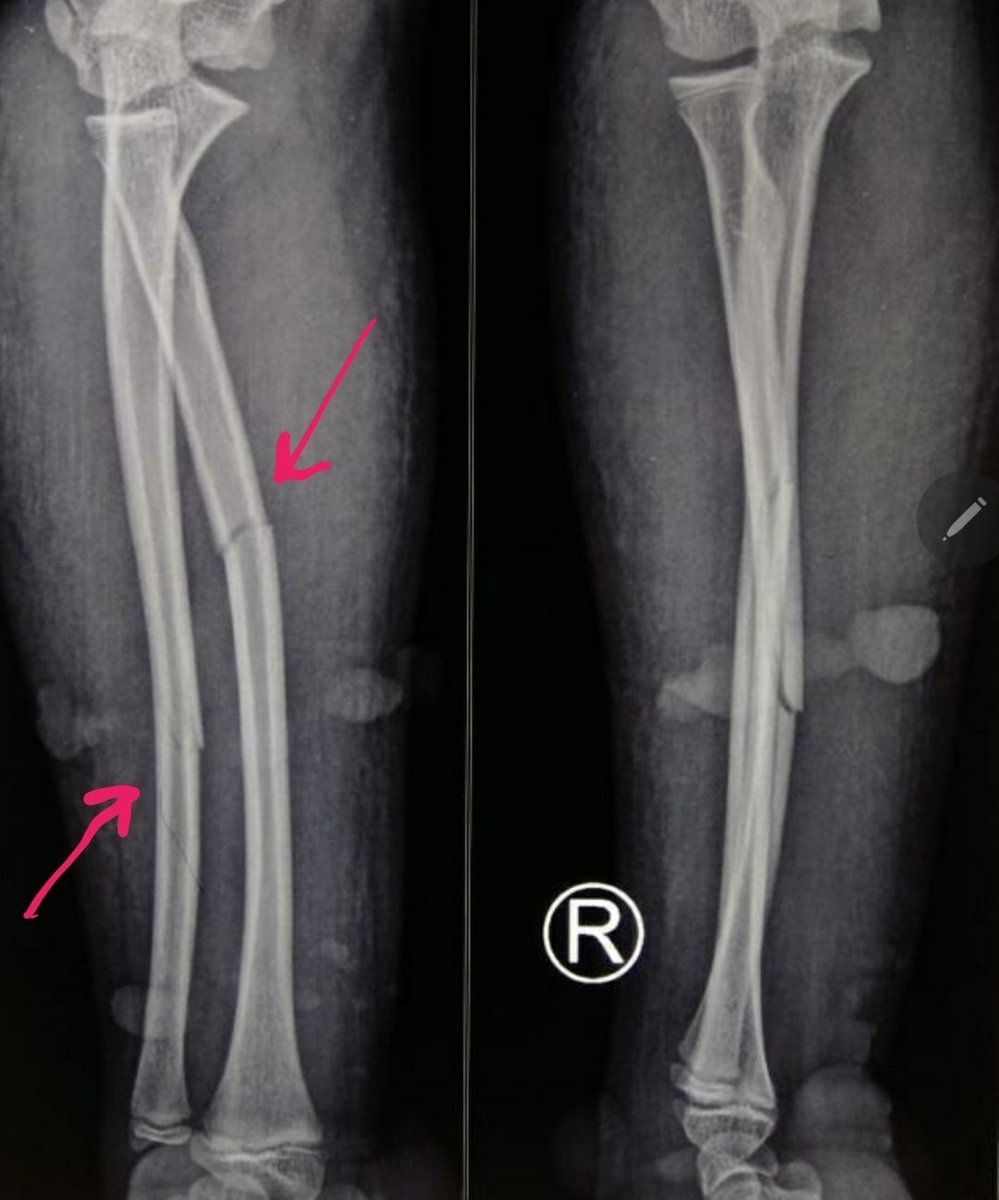

Ada2 lagi ni kelakuan tukang urut pengobatan alternatip patah tulang.

Kasian bgt adeknya, masi umur 9 tahun,bs cacat seumur hidup gara2 penanganan yg sesat!

Pdhl ni patah tulang yg sederhana,tnpa operasi pun bisa,malah dibebat kenceng bgt sama ORANG PINTER sampe hampir membusuk

Jadi ada adek laki2 umur 9 tahun,jatuh saat bermain, trus mengalami patah tulang lengan bawah ..

Kedua tulangnya patah, tapi posisi tulangnya cukup baik, dan tidak banyak bergeser ..

Temen2 bisa liat ya patahannya ga byk geser, bengkok minimal bgt ..

Adeknya kondisinya baik

Sedihnya sama orgtuanya (😡) si adek yg polos tdk tahu apa2(dan cuma nurut aja) ini dibawa ke pengobatan alternatif patah tulang

Kemudian dipasang kayu dan tangannya dibebat kencang bgt

dampak bebat kencang gak pake otak itu apa?aliran darahnya ga jalan!